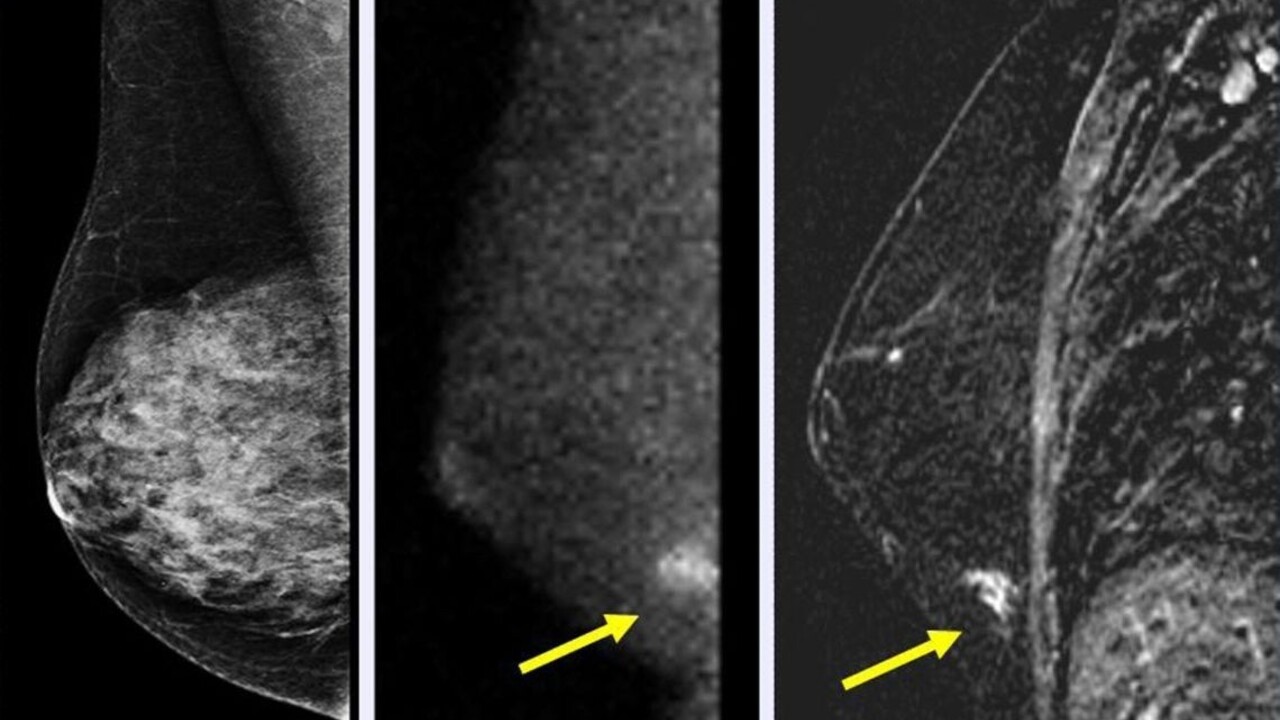

Rakovina prsníka a krčka maternice zabije ročne trikrát viac žien ako komplikácie spojené s tehotenstvom a pôrodom, uviedli vedci z univerzít v kanadskom Toronte, juhoafrického Kapského Mesta a londýnskej King 'College, ktorí sa na štúdii podieľali.

Navrhujú preto posilniť programy očkovania dievčat proti vírusu HPV, ktorý spôsobuje rakovinu krčka maternice, a podporiť prístup k skorej diagnostike rakoviny prsníka.